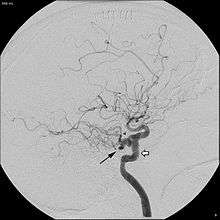

Angiogram demonstrating persistent trigeminal artery, as indicated by the black arrow.

In around 0.1 to 0.6% of individuals, as sampled by magnetic resonance angiography, the trigeminal artery fails to involute and remains in the adult brain, in a condition called persistent trigeminal artery.[3] This condition is more common in women than in men, with approximately 1.8 times as many women having the condition.[6] Knowledge of a persistent trigeminal artery may be important in certain brain surgeries, as the condition is rare and an accidental cut to the artery could lead to hemorrhage.[1] Although the discovery of a persistent trigeminal artery is sometimes an incidental finding, its presence is also associated with various pathological conditions, and must therefore be considered carefully when diagnosing these conditions.[7]